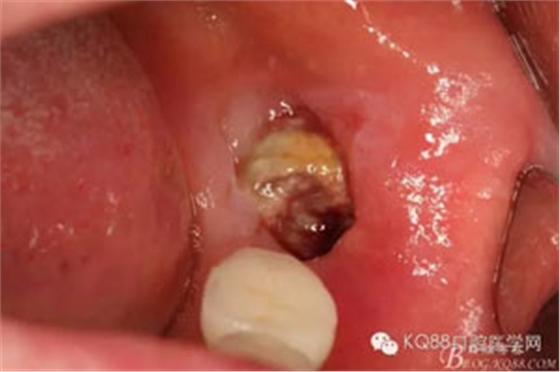

隨著種植修復(fù)技術(shù)的普及,很多患者的口內(nèi)會(huì)有種植修復(fù)體,當(dāng)相鄰的種植修復(fù)體旁邊的牙齒,各種原因無(wú)法保留的時(shí)候,需要拔除,對(duì)于我們來(lái)說(shuō)又是一個(gè)新的挑戰(zhàn)。首先我們要保護(hù)種植修復(fù)體不受損壞,其次是要微創(chuàng)拔除無(wú)法保留的牙齒。這樣才能最大限度的保留種植體周?chē)墓橇?。該患者種植術(shù)前沒(méi)有及時(shí)拔除38。導(dǎo)致修復(fù)兩年后38齲壞,引起臨床癥狀,幸運(yùn)的是沒(méi)有種植修復(fù)37,不然,拔除難度會(huì)加大很多。